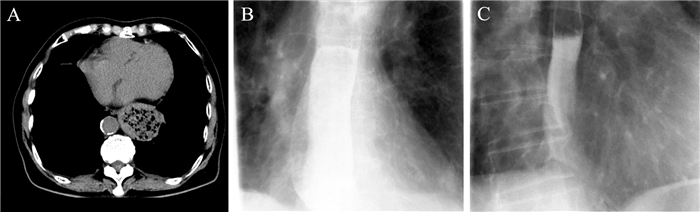

三、辅助检查入院行血常规:血红蛋白137 g/L,红细胞计数4.77×1012/L, 血小板计数111×109/L,白细胞计数15.12×109/L,中性粒细胞百分比85.6%。血液生化:空腹血糖16.86 mmol/L。行血气分析、肝肾功能、电解质、尿常规、粪常规、凝血功能、输血全套、淀粉酶脂肪酶等检验均未见明显异常。心电图检查示:心率68次/分,ST-T改变,窦性心律,完全性右束支传导阻滞,左前分支传导阻滞。外院CT示部分胸腔胃,并食道中上段扩张并内容集聚,膈疝?我院急诊胸部、上腹部CT示部分胃疝入隔上,囊内见散在低密度影及气体影(如图 1A所示),考虑食管裂孔疝可能。由于患者进食立即出现呕吐,CT提示食管内容物积聚,且怀疑胸腔胃嵌顿,行胃钡剂造影及食管镜检查难度大、风险高,故未行相关检查。

图 1 一例老年食管异物梗阻患者CT及食管碘水造影图 A:术前胸部CT; B:术后10 d碘水造影图; C:随防6个月碘水造影图 |

入院后禁食、一级护理、心电监护、胃肠减压,奥美拉唑注射液静脉滴注抑酸保护胃黏膜,补液纠正水电解质以及酸碱失衡等支持治疗。患者主要临床表现为进食后呕吐、吞咽困难、胸骨后及上腹部疼痛,加之外院及本院胸部CT提示食管内容物积聚,诊断报告均考虑食管裂孔疝; 病情急、时间紧,鉴别诊断具有一定难度,因此导致将食管异物误诊为食管裂孔疝,拟行食管旁疝修补术治疗。经左胸第7肋间进胸探查见胸腔内少许淡黄色液体,食管中下段(距贲门口约2 cm以上)明显扩张增粗,食管下段肌层增厚; 切开食管下段,见大量食物残渣潴留于食管腔内,打开膈肌,见贲门口通畅、松弛,胃内无食物残渣,幽门无梗阻,术中纠正诊断为食管下段异物梗阻。行食管异物取出术后予以禁食水,胃肠减压,给予脂肪乳、氨基酸静脉营养、补液,头孢呋辛钠抗感染,注射用奥美拉唑钠抑酸护胃、痰热清清热化痰等对症支持治疗。密切监测血糖、血压,请内分泌科协作给予胰岛素泵持续静脉泵入胰岛素控制血糖良好,请心血管内科协作控制血压良好。术后第10日行食管碘水造影及胸部CT无特殊异常(如图 1B所示),患者开始进食流质,进食流质患者无梗阻、无呛咳,后逐渐过渡到进食软食,顺利出院。

五、随访至投稿日患者精神良好,进食通畅,无吞咽困难,无胸痛、胸闷、气促等不适,大小便正常。手术伤口愈合良好,心肺查体未见明显异常; 复查食管碘水造影(如图 1C所示)及血常规、肝肾功、电解质无特殊异常。

分析导致本例食管异物梗阻误诊原因:①患者为老年女性,入院病史采集否认异物或较大食团吞咽史及吞咽困难史。②临床表现为进食后呕吐、吞咽困难、胸骨后及上腹部疼痛,临床表现与食管裂孔疝极为相似[21]。③外院与本院CT检查见心脏后、食管裂孔上有一最大直径约60 mm的袋状肿块,内有大量低密度物质及散在气体(如图 1A所示),与食管裂孔旁疝影像表现相似,诊断报告均考虑食管裂孔疝。④诊断思维局限,接诊医师在患者否认异物吞食及吞咽阻塞感史后直接排除食管异物梗阻的诊断,未考虑老年患者食管生理变化易引起未嚼烂食团梗阻于食管的可能。⑤病情急,时间紧,患者来院持续呕吐、胸痛,病情较紧急。诊断考虑食管裂空旁疝胸胃嵌顿,需急诊手术解除嵌顿,留给医生观察病情变化,纠正诊断的时间非常短。⑥诊断手段单一局限,患者进食立即出现呕吐,食管内容物积聚,且怀疑胸腔胃嵌顿,行食管钡剂造影及食管镜检查难度大、风险高,辅助检查只能单凭胸部CT,无系统检查从多方面明确诊断。由于临床表现及CT影像提示与食管裂孔疝极为相似,鉴别诊断具有一定困难,导致将食管异物梗阻误诊为食管裂孔疝,开胸行食管旁疝修补术探查时最终确诊为食管异物梗阻。术中探查食管见大块肉质食团梗阻于食管下段,术后分析患者否认吞咽阻塞史及阻塞形成原因可能为:①患者年龄较大,随着年龄增加,各脏器功能衰退, 口腔及咽喉黏膜上皮退行性改变, 导致神经未梢感觉迟钝,加上食管肌肉较松弛,食管异物吞咽困难及吞咽疼痛的主诉不强烈; ②参与咀嚼的肌肉协调功能降低及收缩能力减弱,唾液分泌减少,老年人牙齿脱落,牙槽萎缩, 不匹配的义齿不能很好地发挥咀嚼功能, 食物不能在口腔充分嚼烂研磨而被吞入食管,且老年人食管蠕动功能较差,存在由环状肌发生不规则、局限性挛缩产生的食管第三收缩波,使由第二收缩波下推的未嚼烂的肉块梗阻于下段食管, 形成食管异物; ③老年人自身心理原因,害怕为子女增加负担或怕子女责备,故意隐瞒病史[5, 8]。